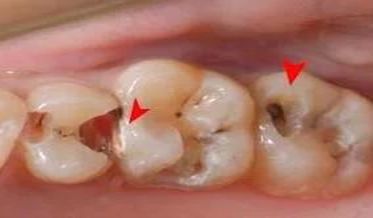

急性牙髓炎可能由牙龈充血发展而来,也可能由慢性牙髓炎急性发作而来。其主要临床症状是剧烈疼痛,痛的性质是自发性阵痛。炎症早期阵痛间隔时间较长,夜间较剧烈,冷热刺激都会引起发作,加剧疼痛。待到炎症晚期牙髓坏死、化脓时,典型的症状为冷的刺激可能使疼痛缓解,而热的刺激会使疼痛加剧。这是由于牙髓组织坏死产生的气体热胀冷缩的缘故。儿童的乳牙和年轻恒压都可能发生急性牙髓炎。

可能发生急性牙髓炎的特点:牙齿出现自发性、阵发性疼痛,多半在夜间出现,您可能无法确认具体是哪颗牙齿,有时还会出现冷热刺激等激惹痛。